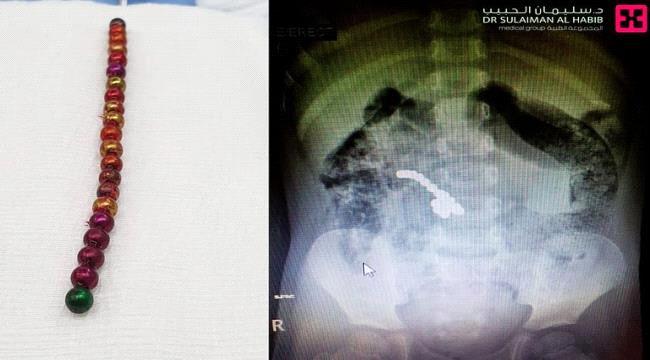

وذكر الدكتور سامي الحواسي مساعد المدير الطبي واستشاري الجراحة العامة بالمستشفى، أنه فور وصول الطفل تم استدعاء فريق من الأطباء المختصين، الذين قاموا بإجراء الفحوص الأولية وعدد من التحاليل والأشعات الدقيقة؛ حيث أبانت بوضوح وجود 21 قطعة مغناطيسية تجاذبت مع بعضها داخل الجهاز الهضمي، مسببةً 6 ثقوب وتلف جزء من الأمعاء وخروج السوائل البطنية وفق صحيفة سبق.

وقال الدكتور “الحواسي”: إن فريق جراحة الأطفال، قرر التدخل السريع للحيلولة دون حدوث أية مضاعفات جديدة وإنقاذ حياة الطفل؛ مشيرًا إلى أنه تم إجراء العملية بالمنظار الجراحي واستغرقت قرابة الساعتين؛ حيث تم فيها استخراج كل القطع المغناطيسية المتمركزة داخل المعدة، بالإضافة إلى معالجة الثقوب، واستئصال الجزء التالف من الأمعاء، وإعادة توصيل الأطراف السليمة مع بعضها.